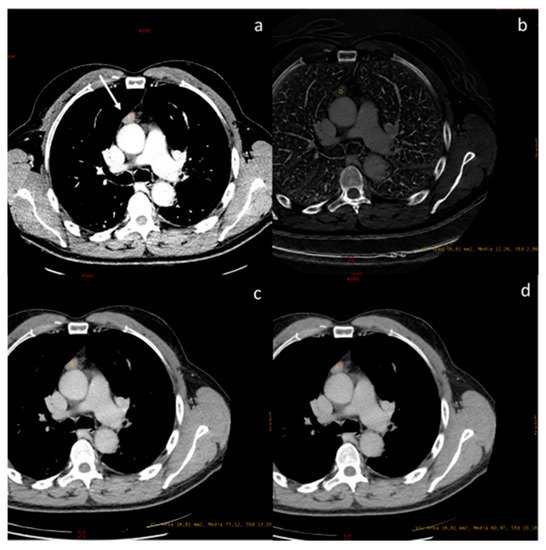

| Chang et al. [63] Prospective study | Korea | To investigate the diagnostic value of DECT in differentiating between low- and high-risk thymomas and thymic carcinomas. | 37 | Discovery CT750 HD; GE Healthcare, Wauwatosa, WI, USA, No C.I. | DECT using a quantitative analytical method based on IC measurement can be used to differentiate among thymic epithelial tumors using single-phase scanning. IHU and IC were lower in high-risk thymomas/carcinomas than in low-risk thymomas. |

| Zhou et al. [64] Retrospective study | China | To explore the utility of DECT parameters in distinguishing thymic epithelial tumours from thymic cysts among lesions <5 cm in diameter. | 56 | Discovery 750HD CT system (GE Healthcare, Madison, WI, USA No C.I. | DECT could distinguish thymic epithelial tumours from thymic cysts (d. < 5 cm). The CT value under 60 keV in the arterial phase has better diagnostic performance. |